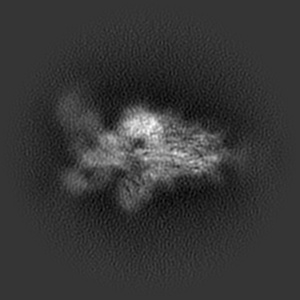

Structure of the SARS-CoV-2 S 6P trimer in complex with the human neutralizing antibody Fab fragment, BG1-24

Sample: Ternary complex of BG1-24 Fab bound to SARS-CoV-2 spike trimer